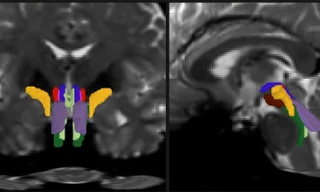

Tác động của AI không chỉ dừng lại ở việc giảm tải hành chính cho bác sĩ. Trong lĩnh vực chẩn đoán hình ảnh, AI đang giúp mở rộng đáng kể năng lực của các chuyên gia.

Amira Romani, Phó Chủ tịch cấp cao phụ trách Đổi mới và Công nghệ của Siemens Healthineers, cho biết một thuật toán AI mới có thể giảm thời gian chụp cộng hưởng từ (MRI) từ khoảng 10 phút xuống chỉ còn 2 phút mà vẫn đảm bảo chất lượng hình ảnh.

Tại một số thị trường Bắc Âu, công nghệ này đã giúp các bệnh viện xóa bỏ tình trạng tồn đọng chẩn đoán kéo dài nhiều tháng.

Khi chu kỳ chụp ngắn hơn, cùng một số lượng bác sĩ chẩn đoán hình ảnh có thể phục vụ nhiều bệnh nhân hơn. Năng lực chuyên môn vì thế trở nên có thể mở rộng quy mô.